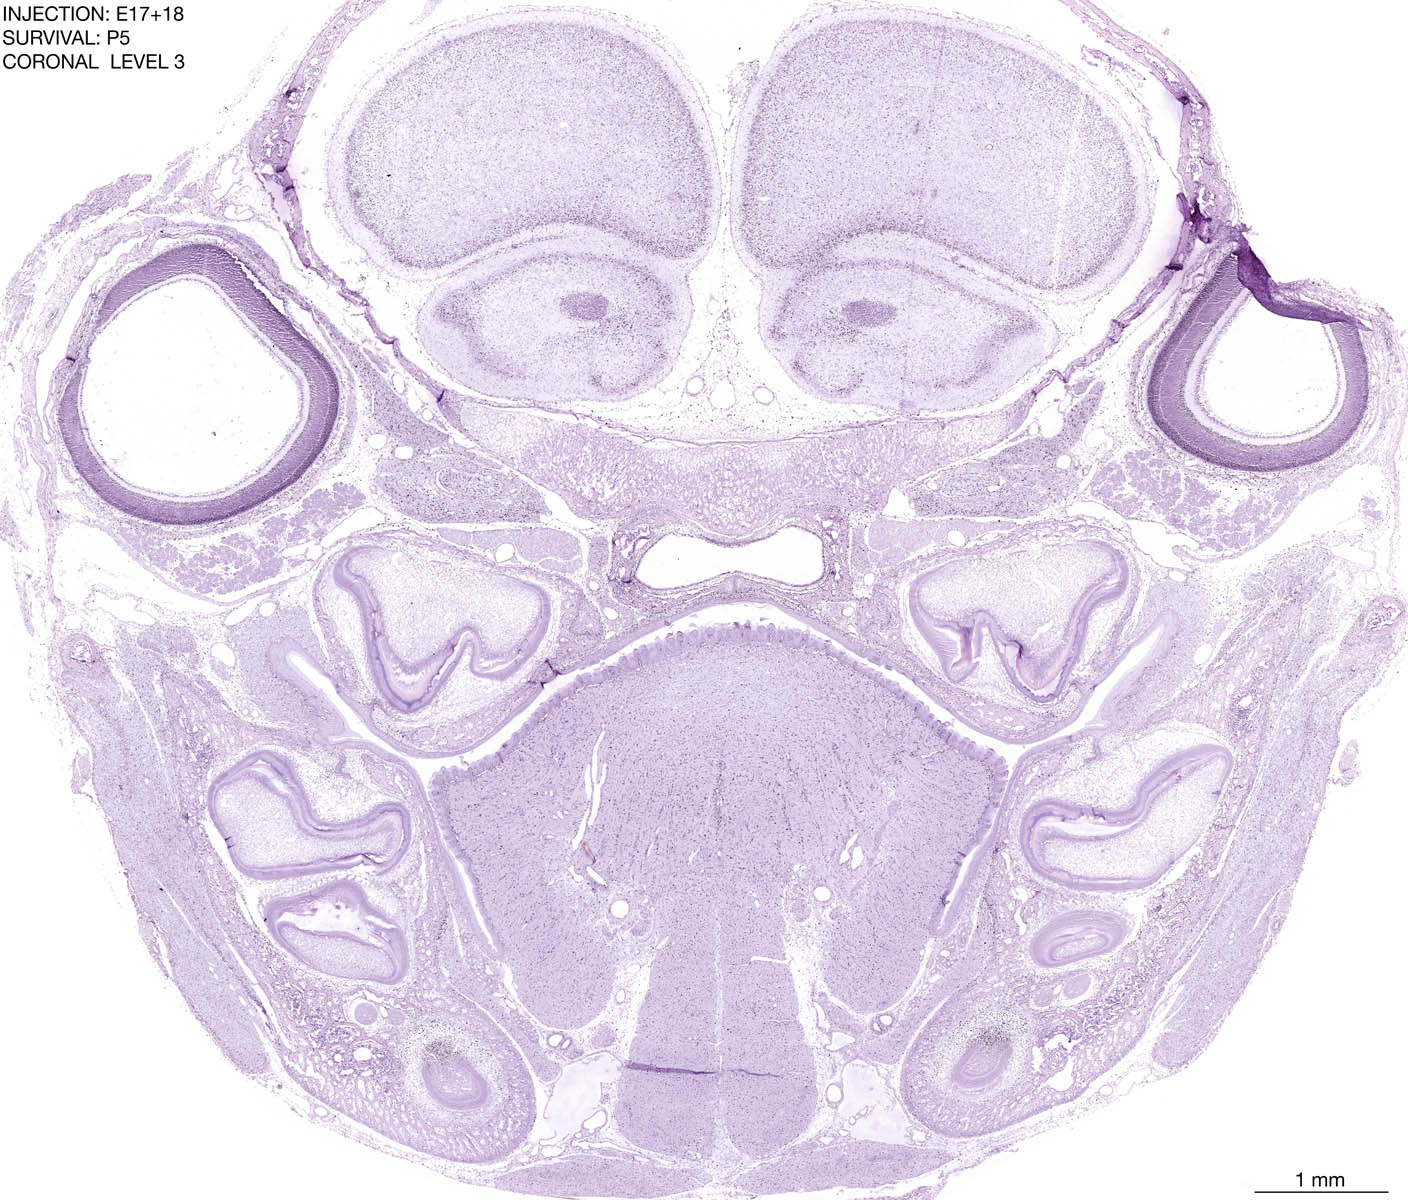

E17+18 P5 Survival The images below are from the brain of a rat that was exposed to tritiated thymidine on E17+18 and survived to P5. Download: Large | High Res Download: Large | High Res Download: Large | High Res Download: Large | High Res Download: Large | High Res Download: Large | High Res Download: Large | High Res Download: Large | High Res Download: Large | High Res Download: Large | High Res Download: Large | High Res Download: Large | High Res Download: Large | High Res Download: Large | High Res Download: Large | High Res Download: Large | High Res Download: Large | High Res Download: Large | High Res Download: Large | High Res Download: Large | High Res Download: Large | High Res Download: Large | High Res Download: Large | High Res Download: Large | High Res Download: Large | High Res Download: Large | High Res